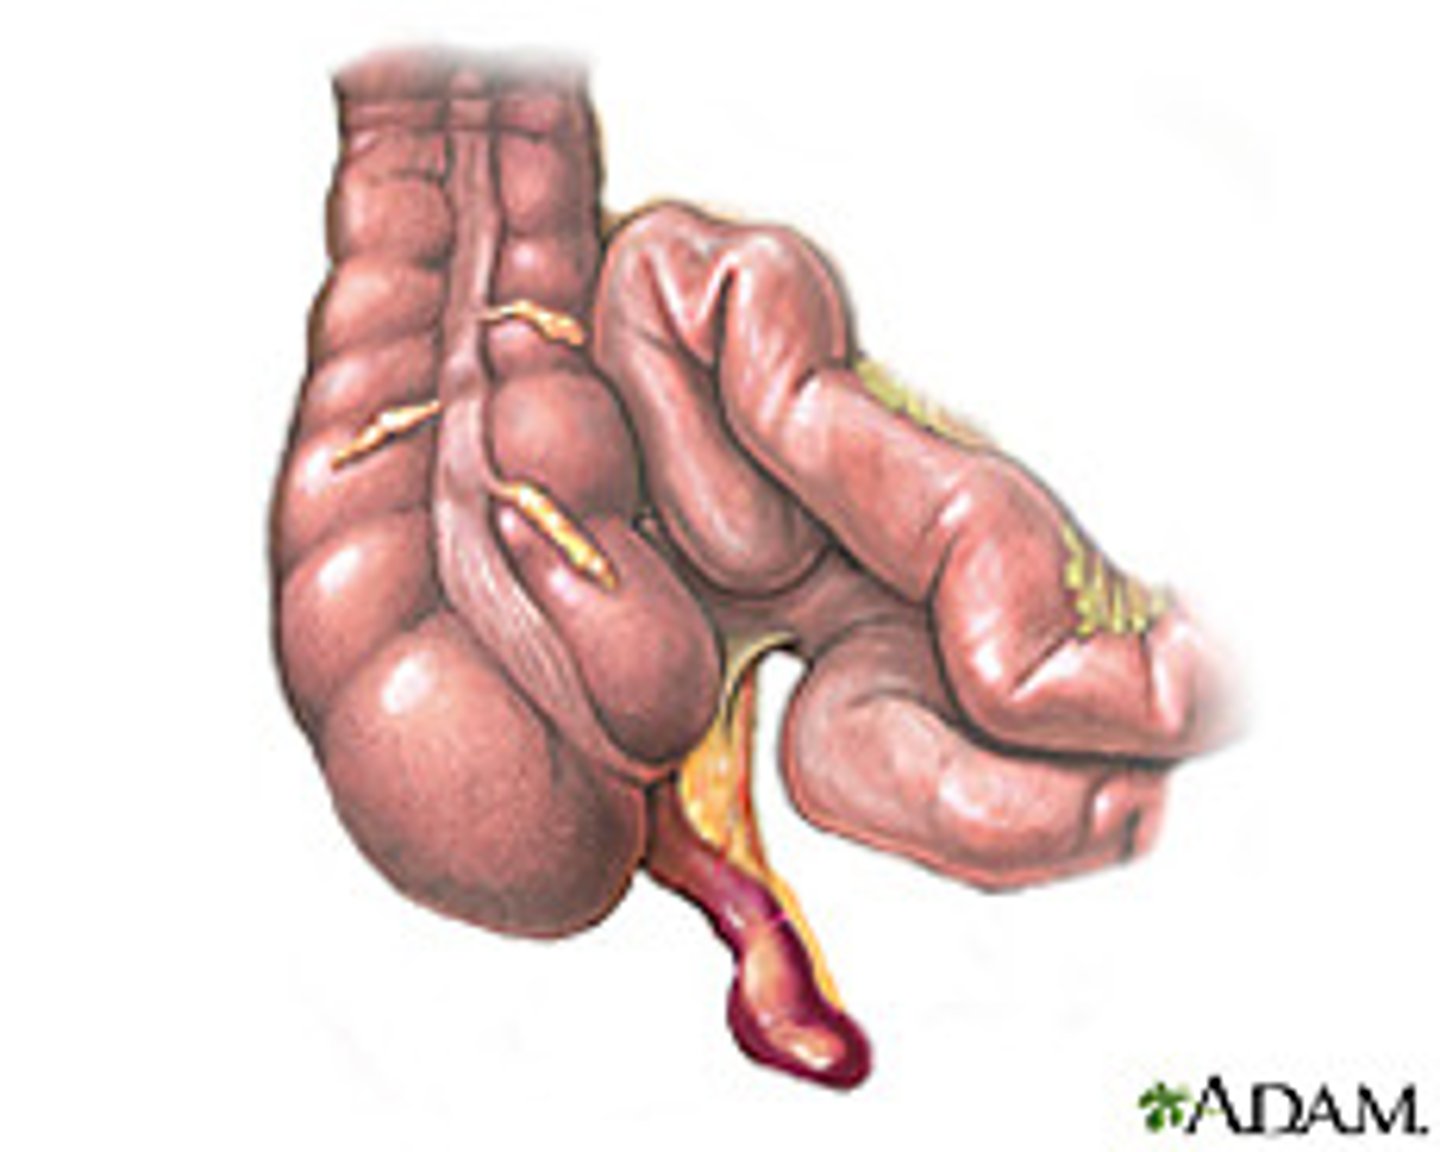

appendicitis

obstruction of appendix by a fecalith, inflammation, foreign body, or neoplasm -> leads to increased intraluminal pressure, venous congestion, infection and thrombosis of intramural vesses

S/Sx: vague pain, pain shift to RLQ, N/V, low fever

appendicitis imaging

CT- diagnostic study of choice in adults, dilated appendix that does not fill w oral contrast, periappendiceal inflammation, increased contrast enhancement of wall, perforation

US- diagnostic study of choice in pediatric pts

appendix

can be seen where it joins cecum, often not seen on CT